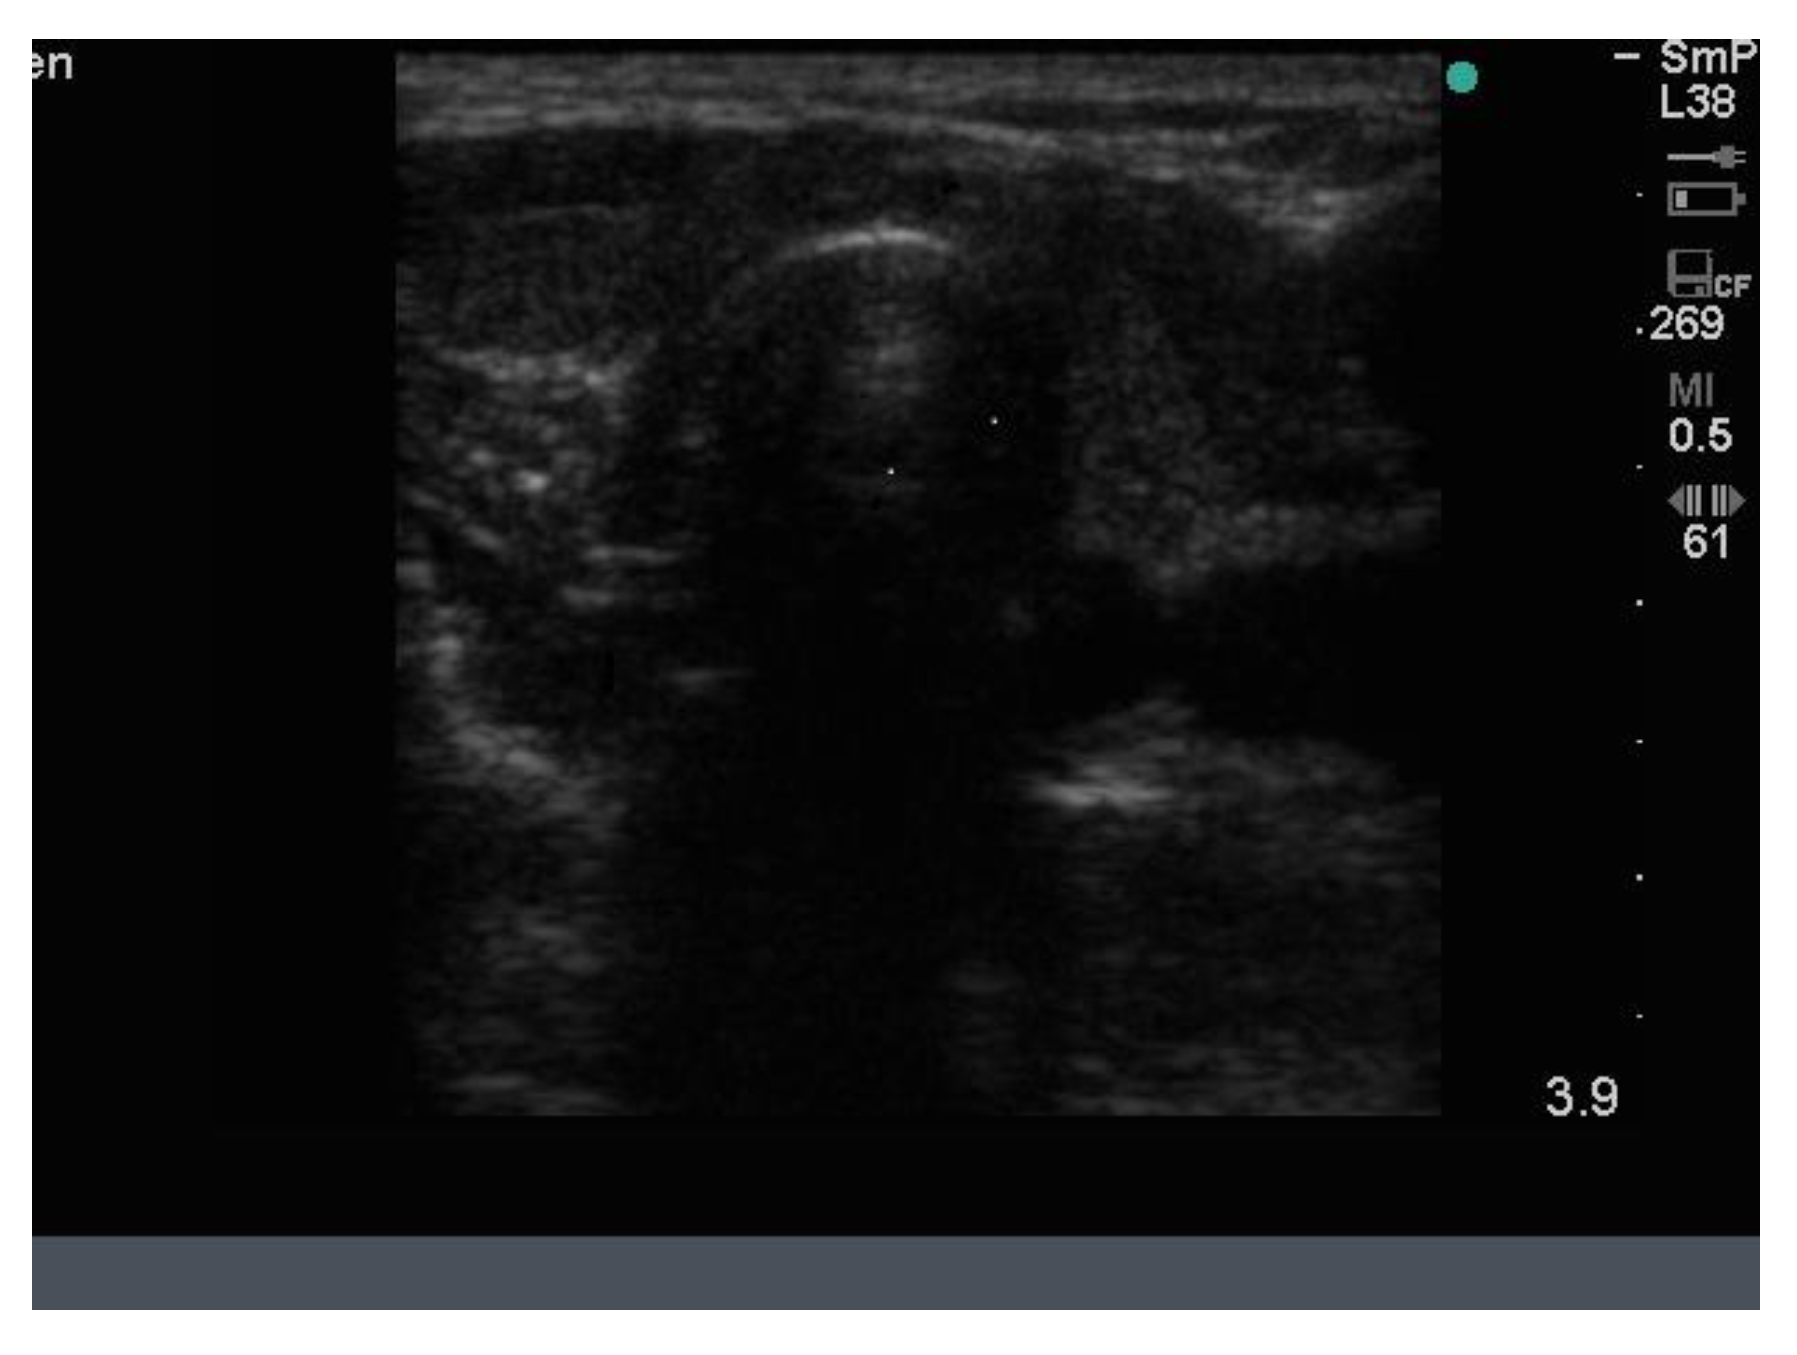

Because the senior author (JW) routinely measures serum calcium, parathyroid hormone (PTH) and vitamin D in his patients, hyperparathyroidism due to a benign adenoma of one of the parathyroid glands appears to be much more common than previously thought. The parathyroid glands are hidden behind the thyroid and so may be obscured by thyroid nodules, although they can often be seen in the longitudinal view below the lobes, as a hypoechoic lesion of around 1 cm in diameter (Figure 18).

Figure 18.

Thyroid ultrasound from a patient with hyperparathyroidism showing a hypoechoic lesion below the right thyroid lobe that was confirmed to be a parathyroid adenoma at surgery.

The parathyroid adenoma is typically hypoechoic by comparison to the nearby thyroid tissue, which is consistent with the author’s experience. However, only about 50% of subsequently proven parathyroid adenomas are seen on ultrasound and even the Sestamibi nuclear scan fails to pick them up in about 30% of cases.